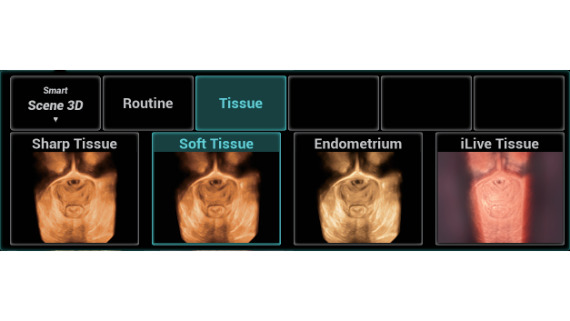

Nuewa I9? ??? ???? ?? ??? ?? ??? ???? ?? ??? ???? ???? ??? ?????. ??? ??? ??? ?? ????? ?? ???? ???? ???? ???? ??? ???? ??? ??? ???? ??? ???? ??? ?? ?????.